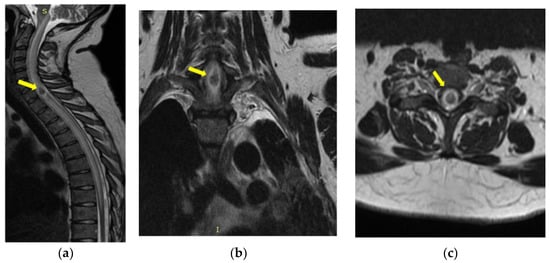

Cervico-Dorsal Intramedullary Spinal Cord Abscess with Aspergillus fumigates following Pulmonary Infection in an Immunocompetent Patient

Mereuta, V.D.; Sava, A.; Stan, C.I.; Eva, L.; Dumitrescu, G.F.; Dobrin, N.; Tudorache, C.; Chiriac, A.; Strambu, I.R.; Chiran, D.A.; et al. Cervico-Dorsal Intramedullary Spinal Cord Abscess with Aspergillus fumigates following Pulmonary Infection in an Immunocompetent Patient. Medicina 2023, 59, 806. https://doi.org/10.3390/medicina59040806